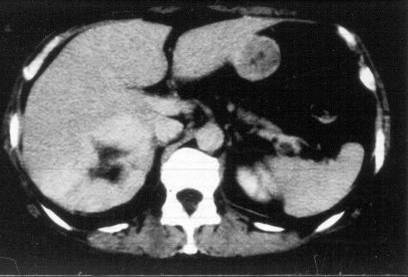

Liver abscess can develop either following the severe inflammation of the biliary ducts and the gallbladder or following a tumorous necrosis or by the spread of an external inflammation to the liver. By the help of the US, a cystic lesion can be seen with multiple internal echos containing gas bubble frequently as well. In order to determinate the further therapy, contrast enhanced CT examination can be needed, if the US imaging of the entire liver was not possible. An avascular intrahepatic lesion can be seen well on the CT with a contrast enhancing wall (sometimes multifocal as well) (Figure 30). An US or CT guided percutaneous drainage can provide a therapeutic result depending on the lesion's size and location (Figure 31).

Figure 30: Abscess in the liver, native CT